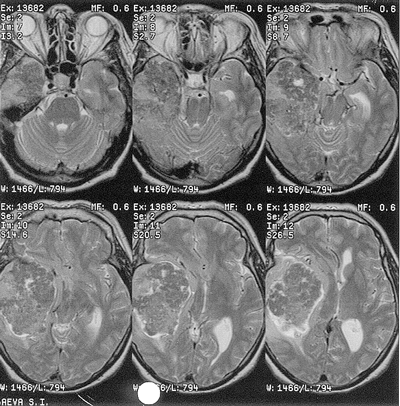

Менингиомы площадки основной кости (рис. 4)

Рисунок 4. Менингиома площадки основной кости. МРТ, Т2-взвешенные изображения, КТ (слева внизу) с контрастным усилением